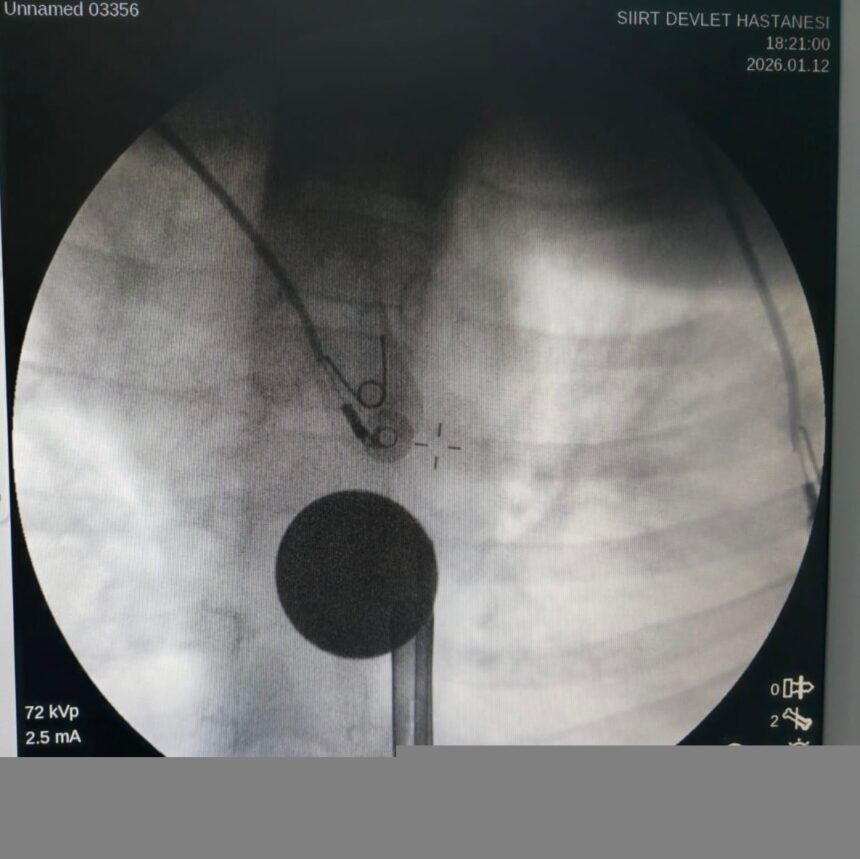

Yabancı cisim yutma şikayetiyle ailesi tarafından Siirt Eğitim ve Araştırma Hastanesi’ne getirilen 8 yaşındaki Y.K., yapılan ilk değerlendirme ve görüntüleme tetkiklerinin ardından ilgili branşlarca operasyona alındı. Y.K.’nın yemek borusuna kadar ilerlediği belirlenen madeni para, gastroenteroloji uzmanı Dr. Yaren Dirik ve kulak burun boğaz hekimi Yasin Gökçınar tarafından müdahale edilerek çıkartıldı. Operasyonun ardından bir süre gözlem altında tutulan Y.K., tedavisinin tamamlanmasıyla taburcu edildi.

Siirt Eğitim ve Araştırma Hastanesi Başhekim Yardımcısı Uzman Dr. Burak Özkan, çocuk hastalarda yabancı cisim yutma vakalarının ciddi riskler oluşturabileceğini ifade etti. Uzm. Dr. Özkan, “Hastanemize başvuran 8 yaşındaki hastamızın yemek borusuna kaçan madeni para, gastroenteroloji ve KBB ekiplerimizin koordineli ve titiz çalışmasıyla herhangi bir komplikasyona yol açmadan başarılı bir şekilde çıkarılmıştır. Operasyon süreci sorunsuz geçmiş olup hastamızın genel durumu iyidir” şeklinde konuştu.